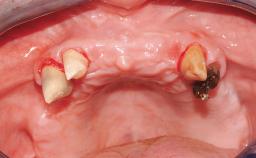

Iliac-Crest Block for Vertical and Horizontal Space Filling in the Anterior Maxilla

A 31-year-old man presented to our clinic 30 days after a motor vehicle accident in which he had suffered a dentoalveolar fracture in the anterior maxilla, including avulsion of teeth 12 and 11 and luxation of tooth 21. He was first treated on the night of the accident in a small city hospital with no oral and maxillofacial surgeon on the staff. A wired retention had been applied and the teeth repositioned to the best of the clinicians’ abilities. When he first presented to our care, the patient showed extrusion of teeth 12 and 11 associated with gingival recession due to bone loss in the anterior maxilla, and the stainless steel wires were still present.

Bone Augmentation Horizontal|Staged|Vertical

Augmentation Materials Autogenous chips|Autogenous block(s)

Bone Volume Horizontally and vertically sufficient Horizontally deficient Deficient vertically or deficient vertically AND horizontally